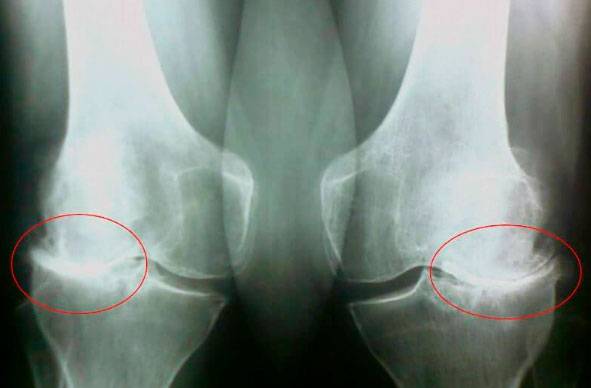

Погляньте на ці знімки, ви бачите, що на правому знімку суглобова щілина відсутня, кістки труться один об одного, викликаючи сильний біль. І цей процес дуже важко зупинити! Через пару років людина стане інвалідом і не зможе себе обслуговувати.

А. Канзюба: Насамперед, це травми та серйозні навантаження. Зайву вагу також надає сильний тиск на суглоби. Малорухливий спосіб життя, стреси, велика кількість солі і цукру в їжі все це розм'якшує хрящову тканину, зношує та стоншує її. Від кожного нового руху хрящ стирається і деформується, кістки починають тертися один об одного, викликаючи нестерпну біль.